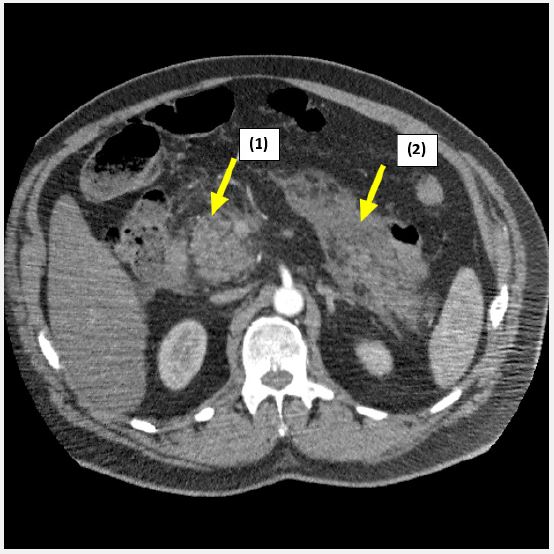

Clinical examination findings were as follows: blood pressure: 165/85 mmHg, heart rate: 90 bpm, SpO2: 97%, respiratory rate: 21. Pain relief was administered using morphine. Laboratory investigations revealed serum lipase of 331.1 U/L (normal <35 U/L). Initial ECG showed no abnormalities, and troponin levels were normal (0.037 ng/ml). CT imaging showed a mildly enlarged pancreas with peripancreatic infiltration, exudate and edema (Figure 1).

Figure 1: CT scan showing a mildly enlarged pancreas with peripancreatic fat and fluid leakage (1), exudate (2) and edema, consistent with acute pancreatitis.